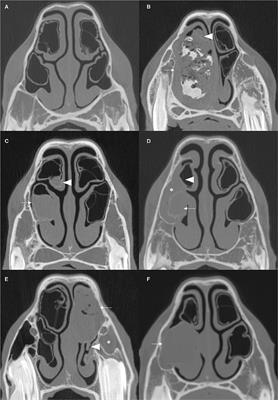

Factors affecting the occurrence of maxillary sinus fungus ball

in Otorhinolaryngology - Head and Neck Surgery